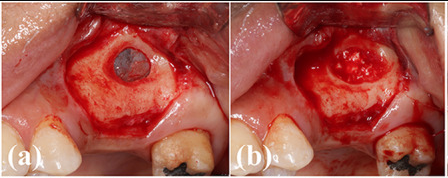

Case photos provided by: Clinical evaluation of 3D printed nano-porous hydroxyapatite bone graft for alveolar ridge preservation: A randomized controlled trial](Clinical evaluation of 3D printed nano-porous hydroxyapatite bone graft for alveolar ridge preservation: A randomized controlled trial - PMC)

Process diagram of clinical procedure; a) Cracked tooth #25; b) #25 Atraumatic extraction; c) Placement of HA hydroxyapatite granules in alveolar socket after atraumatic extraction, with closing of the socket by Cytoplast™ and suturing; d, e) After four months, harvesting of the grafted area with a trephine bur in formalin solution.